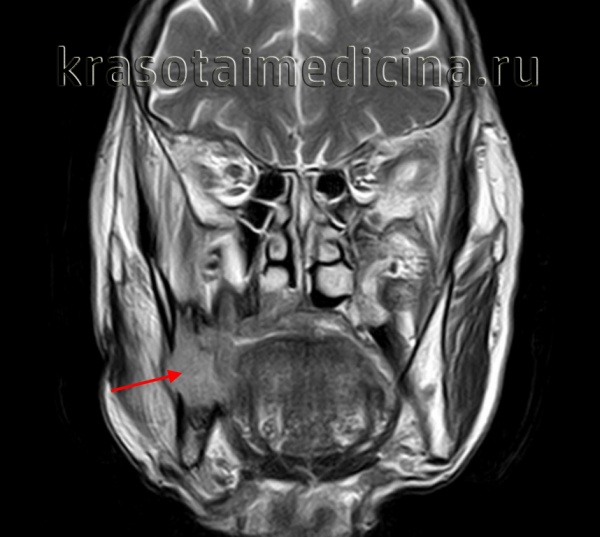

(Слева) На панорамной рентгенограмме у девушки 24 лет определяется однокамерный расширенный участок правого нижнечелюстного канала с четкими контурами. Рентгеновская картина типична для шванномы. Симптоматика у пациентки отсутствует, расширение канала было обнаружено случайно.

(Справа) На панорамной рентгенограмме у этой же пациентки определяется не столь равномерное вздутие нижнечелюстного канала слева. Обратите внимание на некоторое расширение канала сзади от пораженного участка, как на противоположной стороне.

(Слева) На аксиальной КЛКТ у этой же пациентки определяются объемные образования в нижней челюсти с обеих сторон. Обратите внимание на истончение и вздутие язычных кортикальных пластинок.

(Справа) На корональной КЛКТ у этой же пациентки определяется расширение нижнечелюстного канала с обеих сторон. Обратите внимание на вздутие и истончение язычных кортикальных пластинок больше выраженное справа. Корональные изображения лучше всего позволяют оценить концентрическое вздутие канала в случае двухсторонней шванномы.